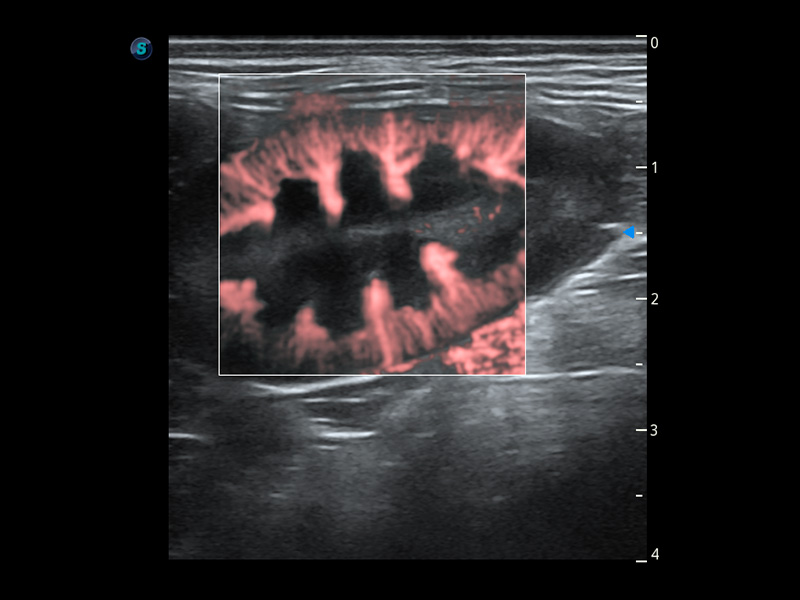

优异的基础图像

(犬)肾脏血流